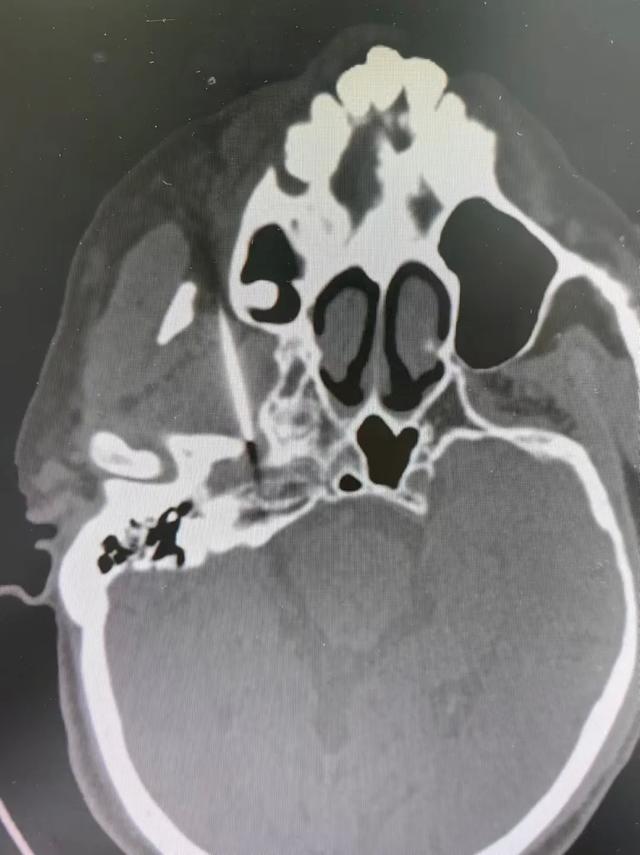

CT引导下颈神经根脉冲射频术(左图),三叉神经半月结脉冲射频术(右图)